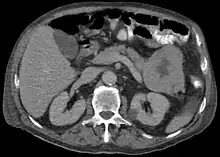

Acinar cell carcinoma of the pancreas

Acinar cell carcinoma of the pancreas, also acinar cell carcinoma, is a rare malignant exocrine tumour of the pancreas. It represents 5% of all exocrine tumours of the pancreas, making it the second most common type of pancreatic cancer.[1] It is abbreviated ACC. It typically has a guarded prognosis.

ACC are typically large, up to 10 cm, and soft compared to pancreatic adenocarcinoma, lacking its dense stroma. They can arise in any part of the pancreas.[2]

Histomorphologically, the tumour resembles the cells of the pancreatic acini and, typically, have moderate granular cytoplasm that stain with both PAS and PASD.[4]

Light microscopy of an acinar cell carcinoma biopsy typically shows granular appearance.[6] Immunohistochemistry is usually positive for trypsin, chymotrypsin and lipase.[6] On genetic testing, altered genes/proteins are typically found for p53, SMAD4, APC, ARID1A and GNAS.[6]